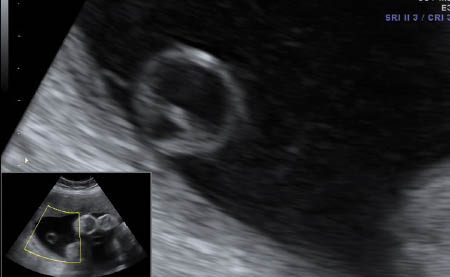

Choroid plexus cyst

Choriod plexus (CP) cysta are cysts that are seen within the substance of the choroid plexus. They can be single or multiple, unilateral or bilateral, and occur with an incidence of approximately 1%. They may result from entrapement of cerebral spinal fluid with tangled villi. As the stroma of decreases with increasing gestational age this fluid is relased and the the cyst resolves. For this reason more than 95% of these cysts resolve by the end of the second trimester [7].

The presence of a CP cyst has been associated with increased risk of trisomy 21, but even more so with trisomy 18 [8]. Seventy-one percent of trisomy 18 fetuses have CP cysts but these are usually associated with additional sonographic abnormalities [9]. The location, size, and morphology do not affect its relation to aneuploidy [9]. Isolated CP cysts create confusion, as its link to increased risk of chromosomal anomalies is less clear [9]. In a metaanalysis of more than 2000 cases with an isolated CP Cyst showed that trisomy 18 was found in one case out of 128 [10]. Based on the findings of this metaanalysis, the American College of Obstetricians and Gynecologists recommends offering amniocentesis in the case of an isolated CP cyst only if the age is >35 or with abnormal serum multiple marker screen [11]. Another large metaanalysis with 246,545 cases found 1346 cases of isolated CP cyst. The study concluded that only when a CP cyst was present with additional risk factors was an amniocentesis warrented [8].